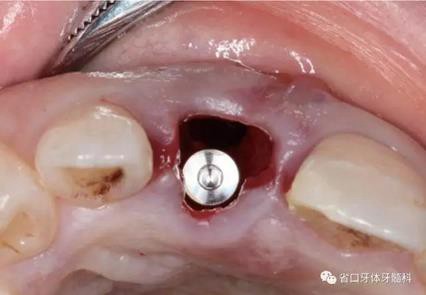

(3)術(shù)后醫(yī)囑與牙齦塑形:術(shù)后予以抗炎止痛對癥處理,7~10天拆 線。術(shù)后3個(gè)月開始逐步調(diào)整臨時(shí)冠并塑形牙齦形態(tài),控制上頜右側(cè)中切牙 近遠(yuǎn)中牙齦乳頭的充盈量和齦緣水平,使得上頜右側(cè)中切牙牙齦形態(tài)與上頜 左側(cè)中切牙盡量相對稱。

圖25 術(shù)后3個(gè)月

圖26 牙齦塑形

圖27 牙齦塑形

圖28 牙齦塑形

圖29 牙齦塑形